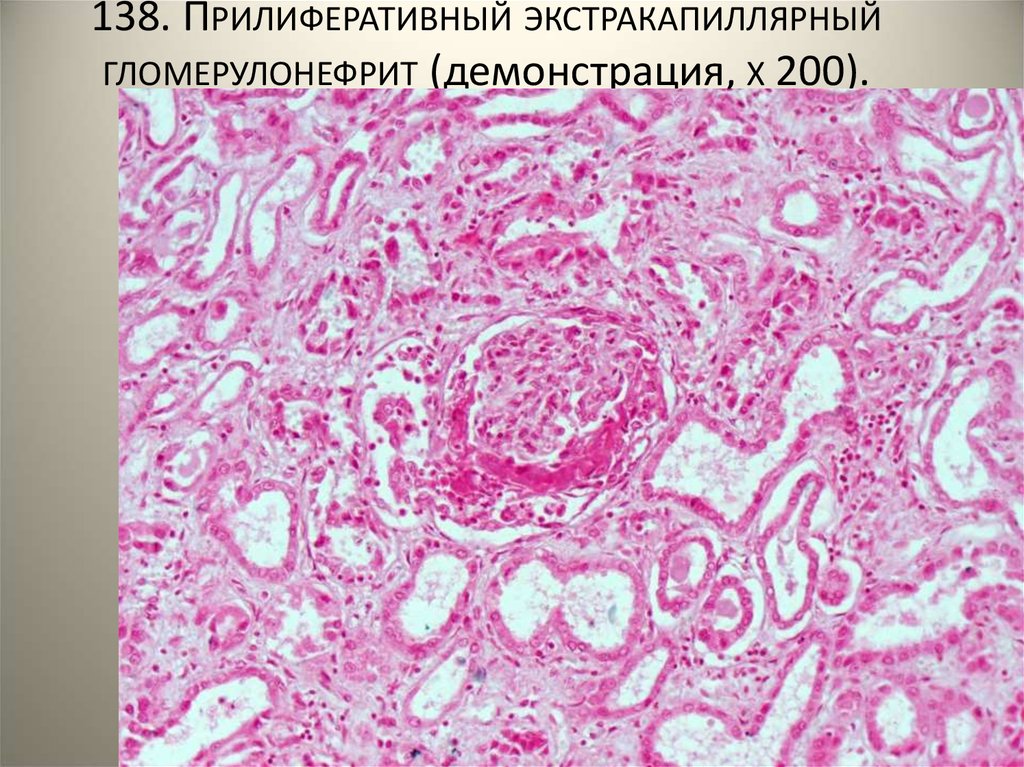

Механизм остро го диффузного гломерулонефрита